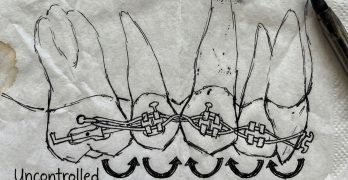

Cierre de Espacios, la Biomecánica que Todo Ortodoncista Debe Saber

El artículo del día de hoy se llama "Space Closure in Orthodontics: A Review" y ha sido publicado en el Journal of … [Leer más...] acerca de Cierre de Espacios, la Biomecánica que Todo Ortodoncista Debe Saber